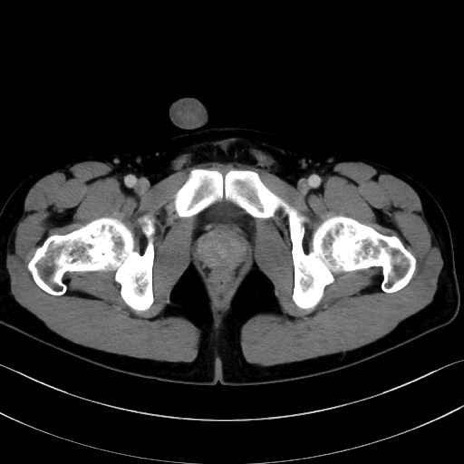

短内転筋(Adductor brevis) のCT画像の解剖

短内転筋 (Adductor brevis)